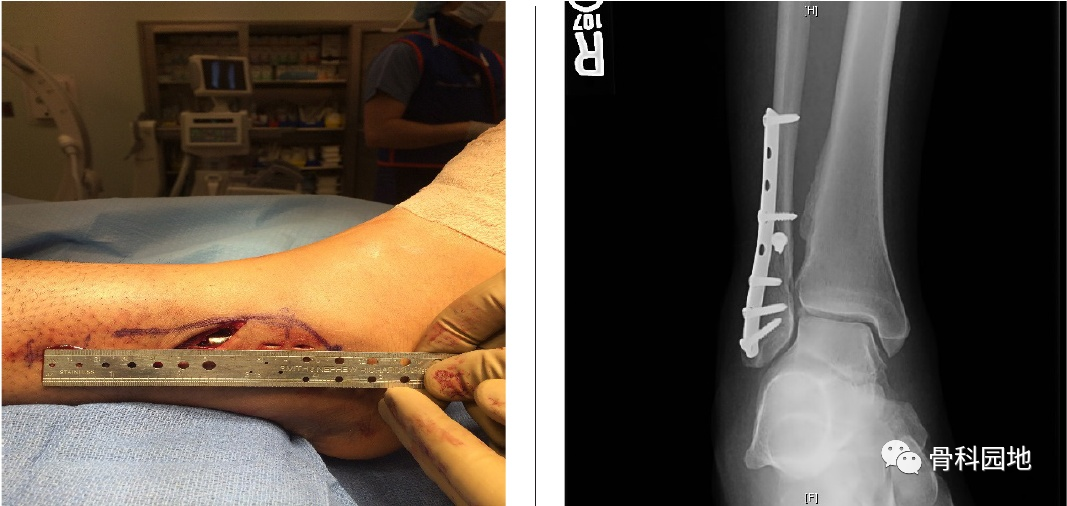

2、在远端3-4厘米的切口上斜置,确定骨折部位。

3、注意避开腓浅神经。将骨折部位的软组织、骨膜或血肿清理干净使用尖头复位钳解剖复位骨折。

4、然后将钢板插入切口,按顺序向近端推入,使钢板远端进入切口,然后向远端推入。一旦在透视镜下确定了正确的位置,我们通常通过切口放置一颗皮质螺钉,以便将钢板固定在腓骨上。然后可以通过小切口置入2颗螺钉。